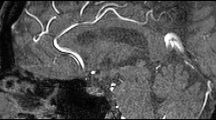

The data is stored in the EBRAINS repository in compressed NiFTi format (*.nii.gz)38. Each raw image stack has an annotated equivalent, designated by a ‘y’ in the file name. Details for each image can be found in the metadata, encoded in the NIfTI1 header format. Each image stack represents a different field-of-view in the cerebrovasculature. Information specific to each image stack can be found in Supplementary Table 1. Maximum projection images of all image volumes are shown in Fig. 4.

MiniVess volumes. Maximum projection images of all raw and segmented (‘y’) image volumes of the MiniVess data are shown for navigation purposes. For clarity, maximum projection images consist of a maximum of 30 slices in each volume. Dark regions within the image volume that appear to have no blood vessels (e.g. diagonal in mv16, top of mv18) likely have blood vessels, but are difficult to see due to ‘shadows’ cast by larger blood vessels above, which are not included in the image volume.